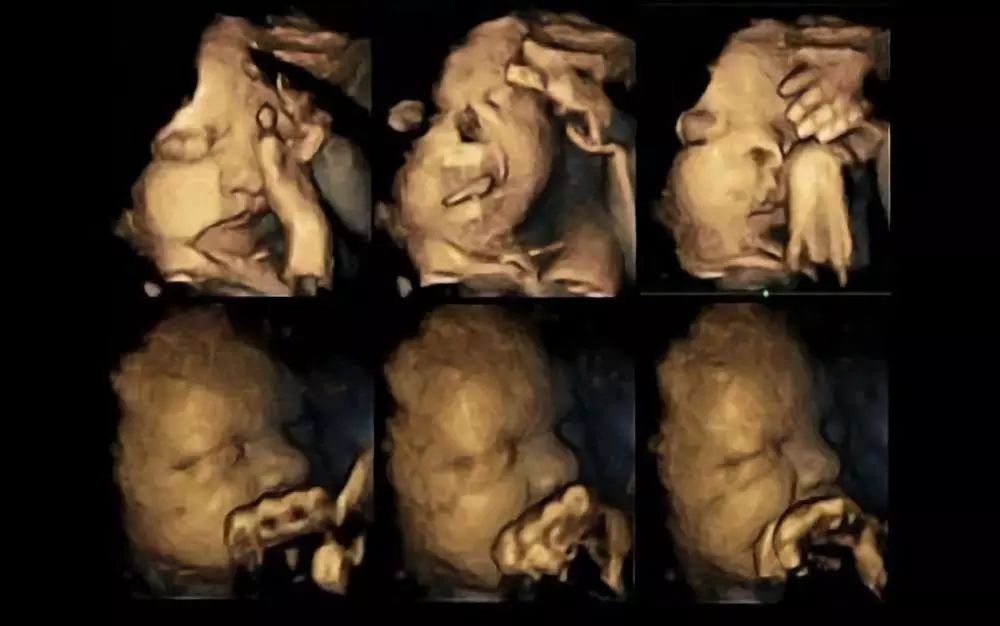

究其原因,女孩的父亲是个老烟民,每天能吸2包烟,不仅在妻子怀孕期间没有戒烟,女儿出生后,他在家抽烟也依然没有任何避讳。 医生告诉他,孩子就是因为天天被动吸烟,才患上了肺癌。 烟民易患肺癌,这我们都知道。 可是那个8岁的孩子,她又不抽烟,她做错了什么呢?! 这,就是二手烟的可怕之处了。 众多研究表明,烟草的致癌物,是在烟丝燃烧的过程中大量产生的。也就是说,二手烟的危害其实远比抽烟还大。 二手烟,里面含有250多种有毒物质,69种致癌物。 而据统计,我国有1.82亿的非吸烟儿童,无辜的他们,平均每天至少有1次机会暴露于二手烟当中…… 更可怕的是,吸二手烟可能对孩子们造成的伤害,还不止肺癌。 呼吸道疾病、厌食、影响智力发育、中耳炎、过敏性疾病、蛀牙、恶性肿瘤…… 吸烟对孩子的危害,真的太多太多了,而越是幼小的孩子,被影响的概率和程度也就越大、越深。 甚至,有些危害,从孩子还没出生就已经开始了。 英国的一项研究揭示,怀孕妇女吸烟有害胎儿健康,可能反映在胎儿的面部表情上。 研究人员对20名孕妇进行了超声波扫描,其中4名孕妇平均每天抽14根,而另外16名孕妇没有吸烟。 研究发现,与不吸烟的孕妇相比,吸烟孕妇的胎儿会出现较多的碰触自己脸部的痛苦表情。

上面为吸烟孕妇的胎儿 下面为不吸烟孕妇的胎儿 就正常情况而言,随着孕期的增加,胎儿的口部和自我碰触的动作应该越来越少,因为胎儿越来越能控制自己的动作。 而吸烟孕妇的胎儿依然有较多这种动作,意味着胎儿的中枢神经系统发育延迟了。 不止如此,有很多证据表明,孕妇暴露于二手烟中,可能会引起早产、胎儿畸形率增加、智力受到影响,严重者甚至会导致猝死。 所以,不仅准妈妈自己不能抽,家里人也尽量不要抽。